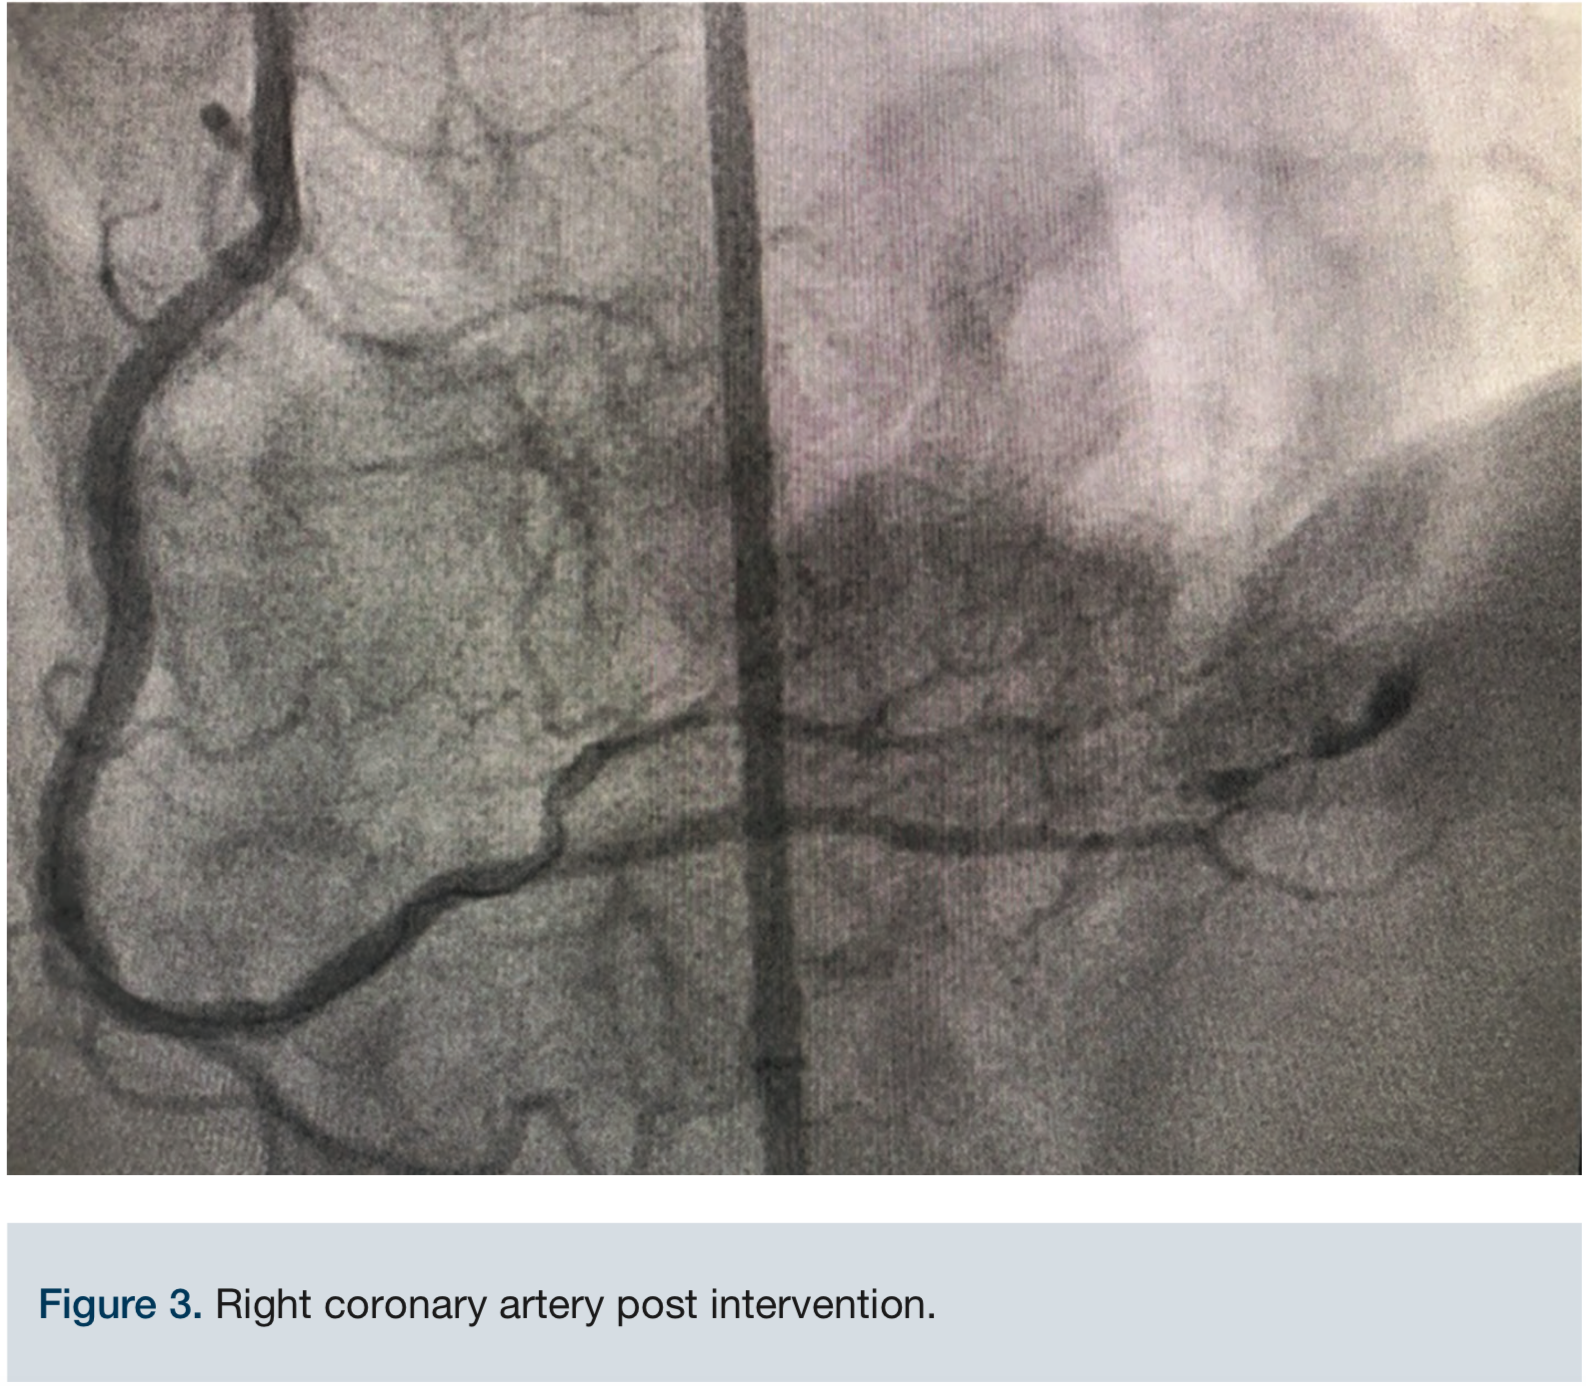

A 68-year-old male was referred to our center for intractable chest pain after a failed intervention to treat ISR of the proximal to mid right coronary artery (RCA) two months prior. The referring cardiologist requested a second opinion and possible Rotoblator (Boston Scientific) rotational atherectomy. After reviewing the case, we determined atherectomy using Rotoblator of the area was contraindicated in view of a stent fracture (Figure 1). It was felt that ELCA (Philips) would give us the safest and best possible outcome, if successful.

Access was obtained via the right common femoral artery. The initial lesion in the mid proximal RCA can be seen in Figure 2. An 8 French (Fr) long Destination sheath (Terumo) was used for maximum support, and a 0.75 Amplatz left (AL) 2 Guide catheter (Boston Scientific) was used for access support and assistance. A Balance Middleweight (BMW) wire (Abbott Vascular) was initially used to advance the catheter into the target artery. We switched to a 300 cm PT choice wire (Boston Scientific) in an attempt to cross the existing stent lumen, with the use of a 6 Fr Guideliner (Teleflex) for additional support. A 2.5 mm x 12 mm balloon (Medtronic) failed to cross the mid RCA stent fracture and ISR. The two markers on the balloon created a too-large catheter diameter, so a 1.25 mm x 12 mm single marker balloon (Medtronic) was chosen instead and successfully crossed. The balloon was inflated to 20 atmospheres (atm) and removed. A second attempt to pass the original 2.5 mm x 12 mm balloon (Medtronic) once again failed. The ELCA catheter was positioned just proximal to the mid RCA ISR within the fractured stent lumen. We started with an 0.9 laser catheter with the tip terminating just proximal to the ISR. An initial fluence of 45 mJ/mm2 was applied and gradually increased to a fluence of 80 mJ/mm2 for a total of almost 5 minutes while the tip was still positioned proximally to the ISR. The laser then was able to advance through the obstruction and was removed. Over the wire, a 2.5 mm x 12 mm balloon was inflated up to 20 atm for 25 seconds and then replaced with a 3.0 mm x 20 mm balloon (Medtronic) inflated to nominal pressure. The same 3.0 mm balloon was used at the very proximal aspect of the ISR as a pre-dilation before two drug-eluting stents (DES) were placed: a 3.0 mm x 18 mm Onyx DES (Medtronic) at the mid RCA and a second 3.0 mm x 30 mm Onyx DES at the proximal to mid RCA. The 3.0 mm x 18 mm Onyx DES stent was deployed at 22 atm for 15 seconds and the 3.0 mm x 30 mm Onyx DES was deployed 20 atm for 10 seconds. Post stent deployment, angiography clearly demonstrated reduction of the stenosis from approximately 99% to <10% at the site of the original stenosis in the proximal to mid RCA. At the end of the procedure, Thrombolysis In Myocardial Infarction (TIMI)-III flow was achieved (Figure 3). Inline flow was successfully restored across the entire RCA. The procedure was uncomplicated, but required the use of significant amounts of contrast (500 mL) and fluoroscopy (81.1 minutes). The patient was discharged the following day without incident, and has thus far remained asymptomatic throughout his follow-up with his referring cardiologist.